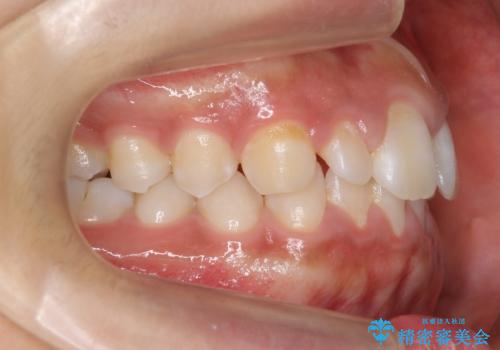

当初はワイヤー矯正を希望されていましたが、右上7番の頬側に咬頭があり、ブラケットを貼ることが難しいため、こちらからマウスピース矯正をお勧めしました。

前歯のすきま 矯正治療とセラミックで小さな歯を形良く

- 前歯のすきまを気にして来院。

左上の2番が生まれつき小さく、スペースが余っていました。

右上の2番もやや小さめでしたが、相談の上、左上2番のみセラミックで形を整えることとしました。

そのほかの隙間はマウスピース矯正で閉じることにしました。